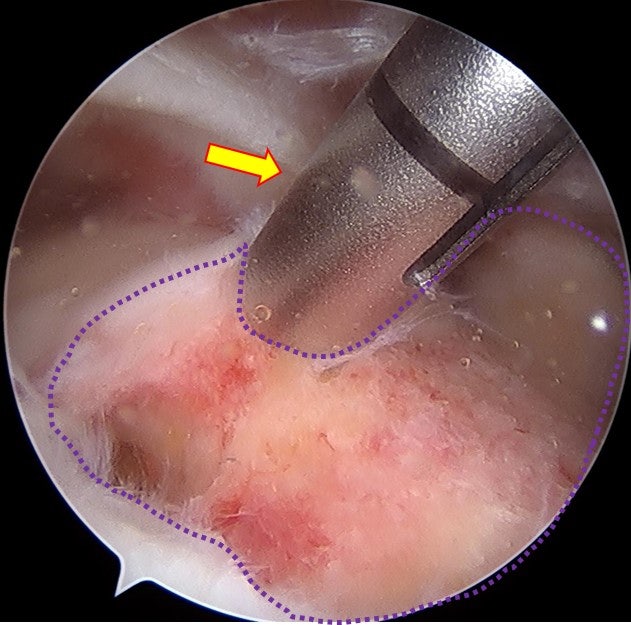

이러한 경우 회전근개가 원래 상완골의 대결절까지 복원이 되어야 하는데 그렇게 되지 않을 가능성이 많습니다. 그래서 환자분의 수술 계획은 최대한 봉합술을 시행하고 복원되지 않는 부위는 인조인대(allomend)를 이용하여 보강하기로 계획하였습니다.

수술을 원래 계획했던 대로 allomend 를 이용하여 회전근개 봉합술 및 봉합술을 시행하였습니다. 수술 직후 MRI 영상으로 확인해 보았습니다.